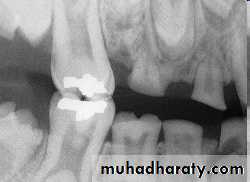

Dental floss abrasion. Note the obliteration of the pulp chambers and reduction in size of the root canals.